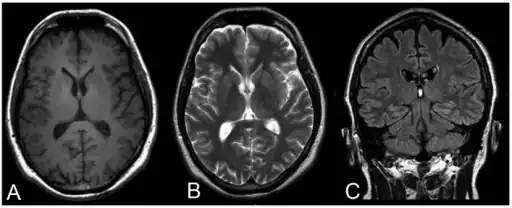

| Progressive myoclonic epilepsy type 1-a,b) MRI c) FLAIR | |